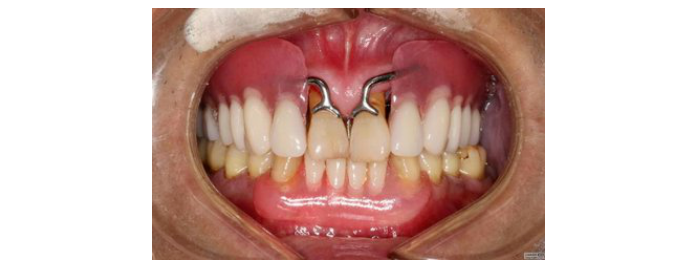

图1:可摘局部义齿

活动假牙是通过金属装置将假牙固定在其他天然牙和黏膜上,使用者可自行摘戴。

但活动假牙比真牙,更容易藏污纳垢,滋生细菌。

若假牙长期清洁不当,附着在假牙上的细菌,则不仅会影响假牙佩戴者的口腔卫生,还可能引发牙周炎、义齿性口炎等问题。

致炎细胞因子还可进入血液循环,作用于全身,可成为心脏病、高血压等多种疾病的隐患。

活动假牙一般有卡环。卡环扣在邻牙上作为支撑,这样稳定性坚固性也会较好。

但是每天取几次,对邻牙会造成一定的危害。

并且邻牙上的卡环也不好清洁,容易堆积菌斑。邻牙也更容易出现龋坏。